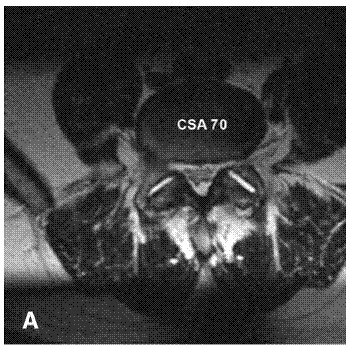

La resonancia magnética es el examen de eleccion.